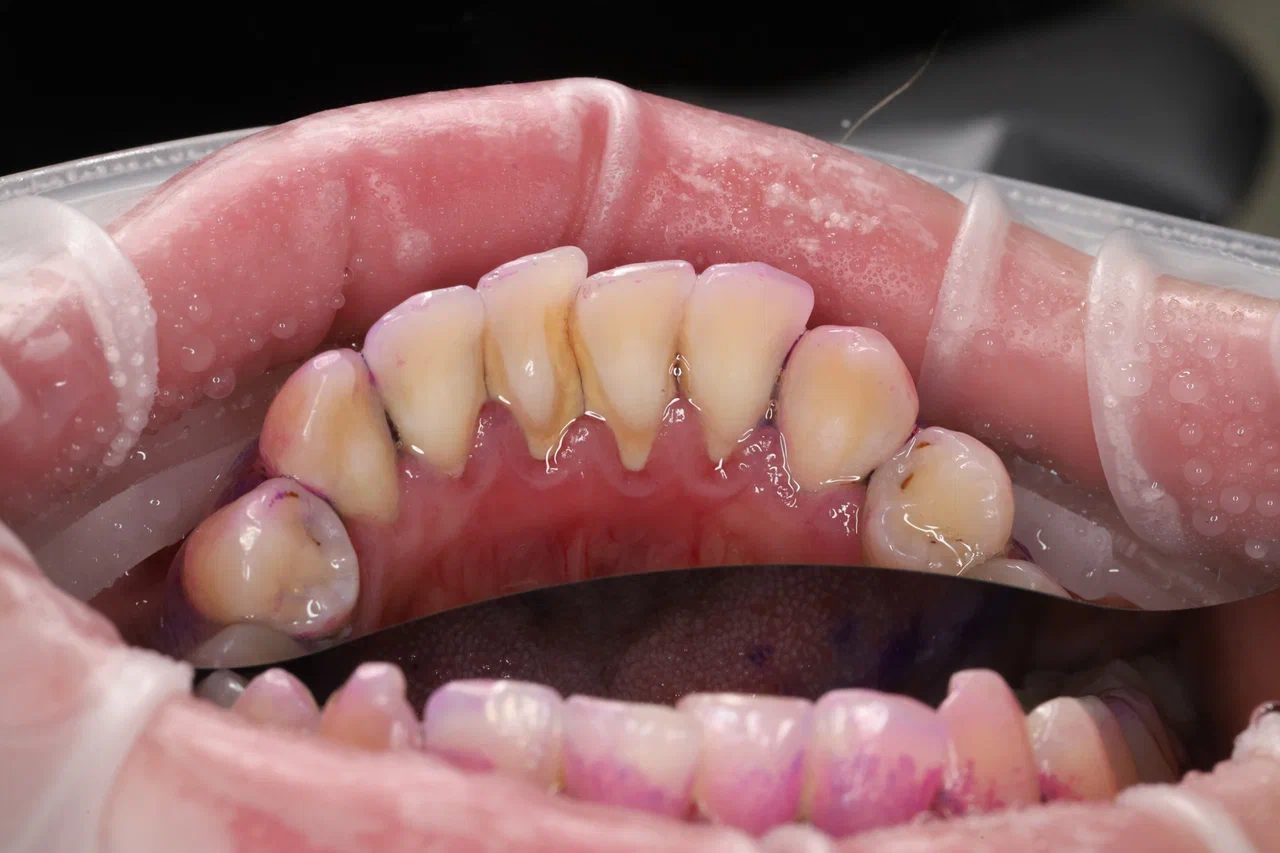

Пациент обратился с жалобами на кровоточивость дёсен и неприятный запах изо рта.

Мы провели диагностику и назначили пародонтологическое лечение. Сначала выполнили профессиональную гигиену полости рта, затем обработали пародонтальные карманы над- и поддесневые по протоколу FMD по сегментам. Пациент обучен правильному домашнему уходу и находится под регулярным пародонтологическим контролем.